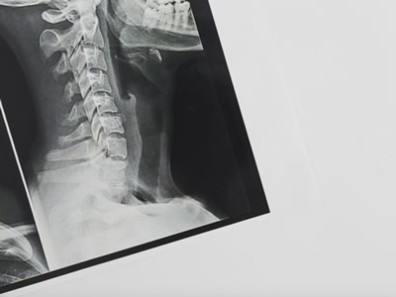

Radiografia Lateral de Mandíbula

Indicada para pesquisar corpos estranhos, delimitação de áreas patológicas, localização de cálculos salivares, terceiros molares inferiores e avaliação de fraturas mandibulares. Pode ser direcionada para ângulo e ramo ou corpo mandibular.